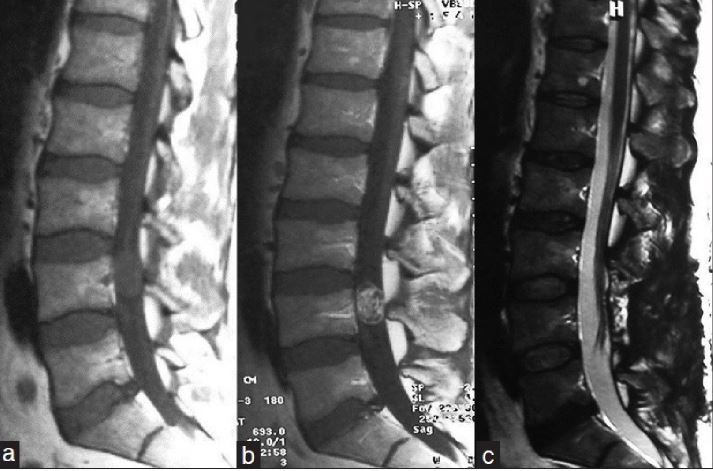

Q

-modality -weight -orientation -body part -contrast -abnormality

A

-MRI -T2 -saggital -cervical spine -can’t tell with T2 -intramedullary cervical cord tumor

18

-MRI - T1 -sagittal -thoracic spine -yes -hemangioblastoma